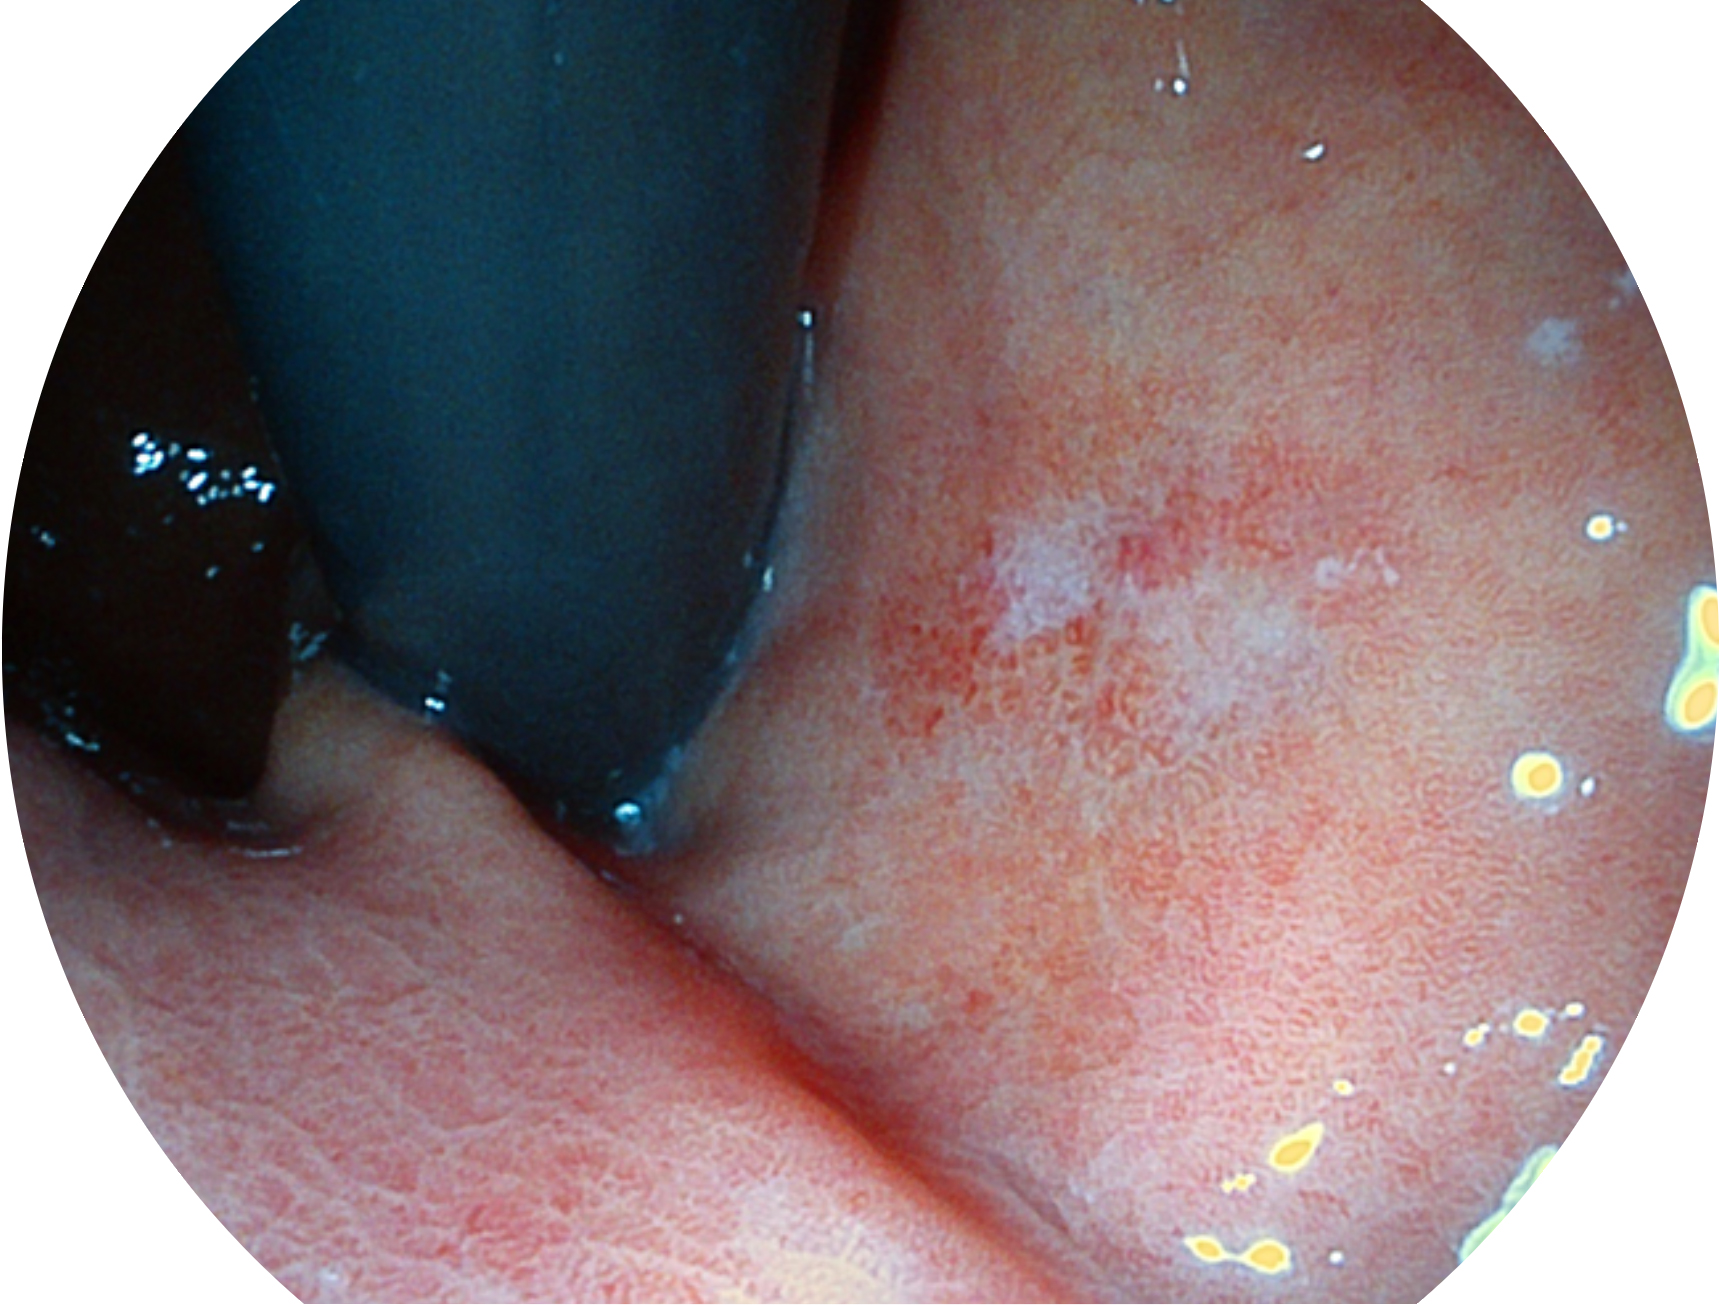

開立新開發(fā)的內(nèi)鏡染色技術(shù),主要是基于多波長LED 光源的開發(fā),VLS-55Q 四波長LED 光源是由四個不同顏色的LED光按照相應(yīng)照明模式所規(guī)定的特定發(fā)光比例進行合束后形成,合束后形成的照明光的光譜由紅光、綠光、藍光及藍紫光這四個不同的波段范圍構(gòu)成。具有更高光譜自由度,通過光譜比例的控制,實現(xiàn)了聚譜成像技術(shù),英文全稱為“Spectral Focused Imaging, SFI”,縮寫為“SFI”和光電復(fù)合染色成像技術(shù),英文全稱為“Versatile Intelligent Staining Technology, VIST”,縮寫為“VIST”。